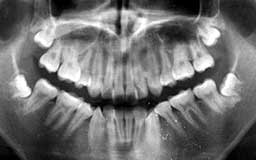

★ Oさん 61歳

Oさんもそんななかのひとりです。来院直後の6年間にブランクがあって、その時失った下

顎の前歯部を除けばかなりの状態をキープしているといえます。61歳としては余りにも条

件が良すぎたためにメインテナンスを積極的に勧めなかったことが少し悔やまれます。

| Oさん 初診時 61歳 男性 上顎臼歯部に中程度以上の歯槽骨破壊が認められるが残存する歯の数は多い |

Oさん 20年後 81歳歳 補綴(ほてつ)物が多いことに不満を感じるが親知らずを含む残存歯数27本は立派 |